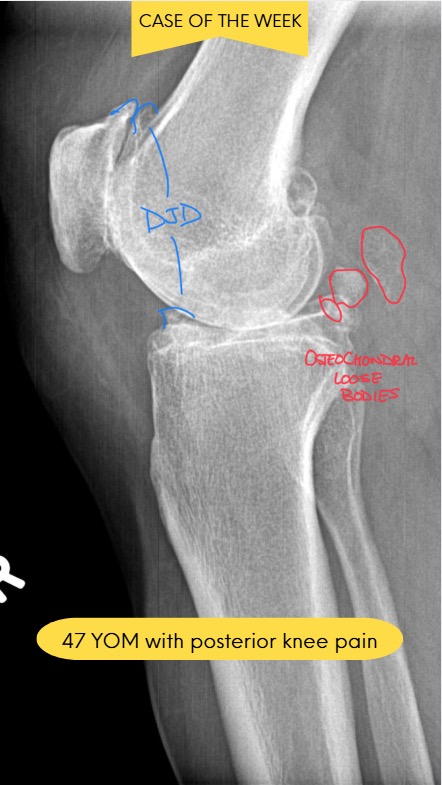

Chondrocalcinosis and CPPD: Kinetic Radiology

DACBR’s Guide to Chondrocalcinosis (CPPD) for Chiropractors

February 6, 2026